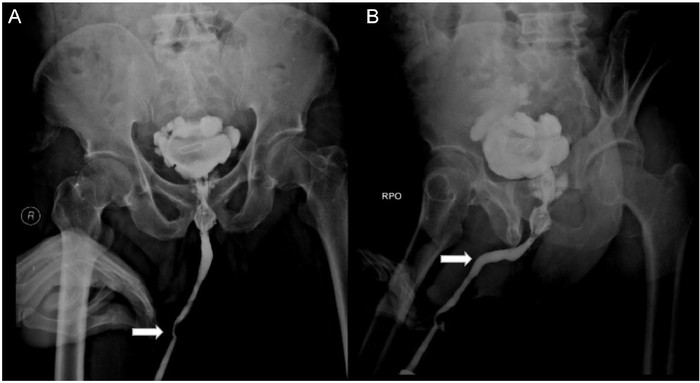

Sebuah hasil rontgen menunjukkan ada sekitar 800 jarum 'susuk' yang bersarang di tubuh seorang wanita. Radiografi perut dari pasien yang sama juga menunjukkan jarum berada paling banyak di area panggul. (Foto: Journal of Radiology Case Reports)